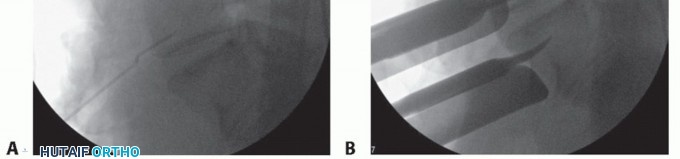

- TECH FIG 4 • AP (A) and lateral (B) fluoroscopic images showing midline positioning and screw trajectories of stand-alone ALIF device.

Typically, a single interbody cage that spans the disc space is selected, with graft material packed on both sides within the implant. This is positioned in the center of the interspace using product-specific instruments (TECH FIG 4A).

Locking screws are directed cephalad and caudad either through the cage device or through a metal faceplate that attaches to the cage (TECH FIG 4B). Knowledge of productspecific screw trajectories and starting points is paramount as they may be either symmetric about the midline or translated left or right to allow safe passage of the drill between the iliac vessels. - Adjunct Treatments